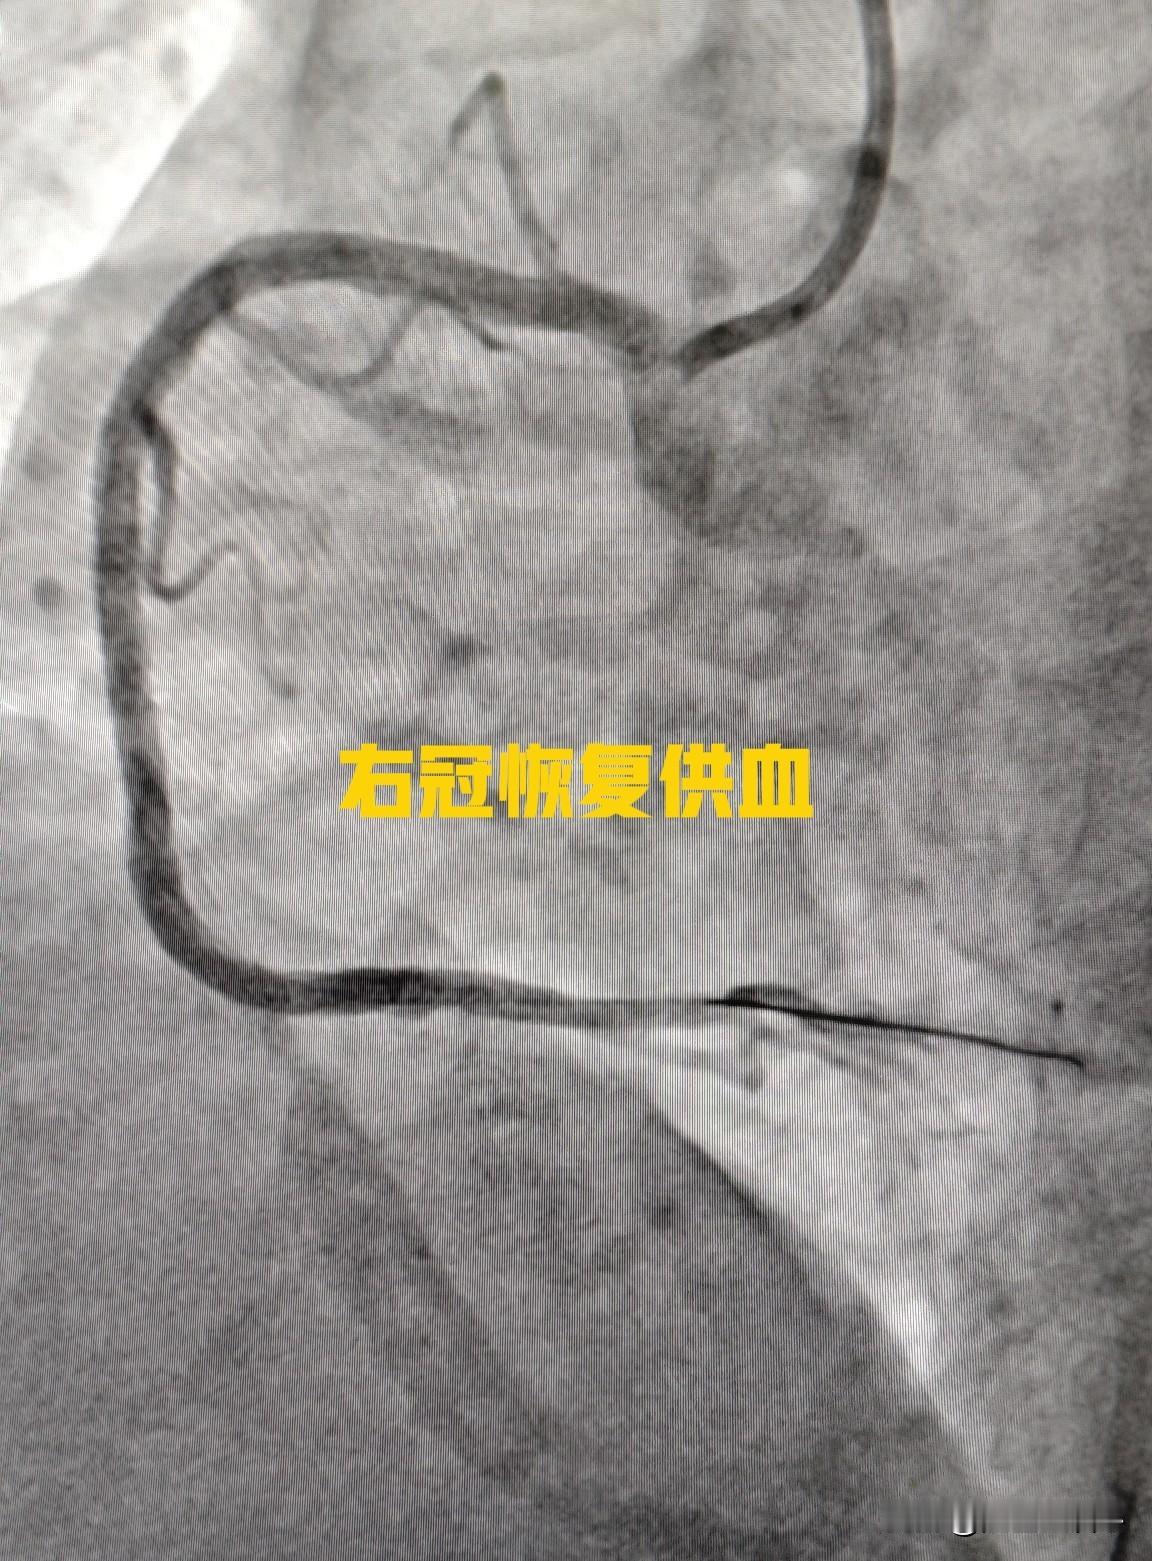

高龄女性,多根血管狭窄,耐受性差,低体重,分次手术更安全。75 岁女性患者,三支病变,前降支长节段重度狭窄,回旋支闭塞,右冠重度狭窄。 回旋支细小,供血范围相对比较小,有侧支循环,战略性放弃,就不开通了。主要精力放在右冠和前降支上面。 考虑到患者高龄,耐受性差,造影剂量大以后会影响到肾脏,引起肾功能恶化。今天先右冠做了2 枚支架。让患者休息一段时间后,身体休养一下。过段时间再来做前降支。